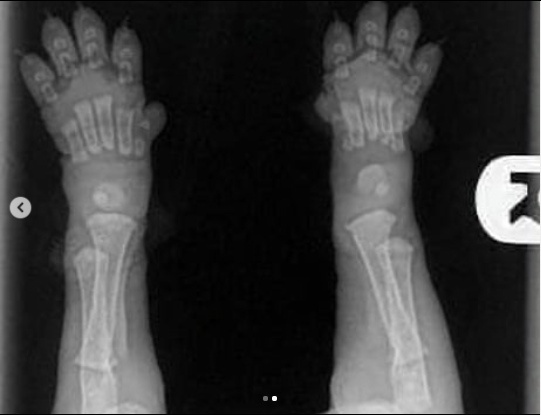

Когда вы получаете своих щенков в возрасте 8/10 недель, пожалуйста, помните об этих фотках. Видите их кости еще даже не соприкасаются. Вы заметили что все щенки с большие гибкие лапами и шаткими движениями, их суставы полностью состоят из мышц, сухожилий, связок, покрытые сверху кожным покровом. Кости не могут плотно прилегать друг к другу пока не имеют настоящего гнезда - т.е. сформированного сустава. И чтоб защитить кости щенка от деформации Природа сделала так, что щенки много бездельничают м спят.